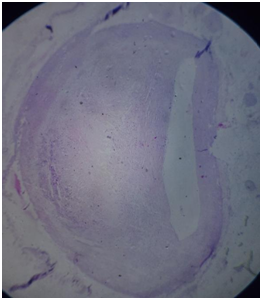

Histopathology report stated lungs showed few hyper inflated alveolar spaces with breakdown of alveolar septa, the spleen had oedematous and congested parenchyma. Liver showed extensive hepatocellular necrosis, fatty change & congestion. Section from coronary artery showed an intimal lesion composed of macrophages, lymphocytes, fibroblasts, smooth muscles and cholesterol clefts occluding the vascular lumen (80%), showing atheroma of coronary artery (Figures 6–8).

Figure 6 Low Power (4x) view showing a large vessel with an occlusion atheromatous plaque.